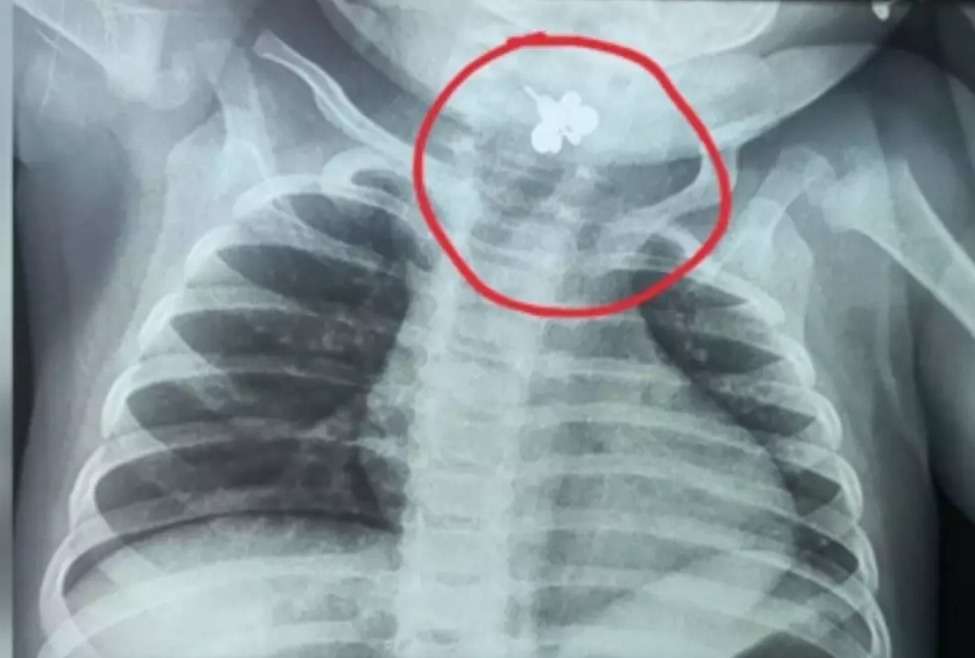

Un caso que sorprendió a médicos y familiares ocurrió en Caacupé, Paraguay, donde una bebé de apenas 10 meses pasó cinco días con fiebre constante y sin poder alimentarse. Al inicio, los síntomas fueron tratados como una infección común, pero al no mostrar mejoría, los doctores decidieron hacer estudios más profundos. Fue entonces cuando una radiografía reveló algo inesperado: la pequeña tenía un anillo atorado en la garganta, el cual había aspirado accidentalmente.

El hallazgo encendió las alarmas y activó un protocolo de emergencia. La bebé fue trasladada de inmediato al Instituto Nacional de Enfermedades Respiratorias y del Ambiente (Ineram), en Asunción, donde un equipo especializado logró extraer el objeto con éxito.

El anillo, cuya ausencia no había sido notada, probablemente estaba en el área donde la menor solía jugar o dormir, lo que retrasó su detección y complicó el diagnóstico inicial.

Tras la intervención, la bebé permanece internada en terapia intensiva bajo observación médica, como medida preventiva para descartar infecciones o daños en las vías respiratorias. Especialistas recordaron que los menores de dos años suelen llevarse objetos pequeños a la boca, lo que representa un riesgo grave.